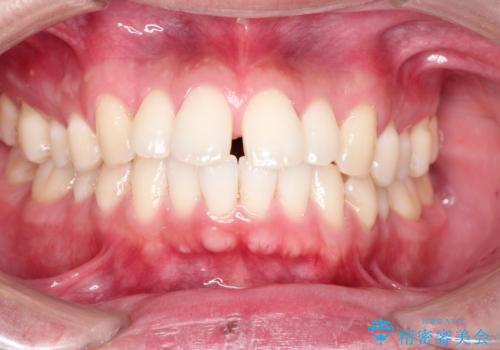

前歯の隙間を閉じたい 口元も下げたい ハーフリンガルによる抜歯矯正